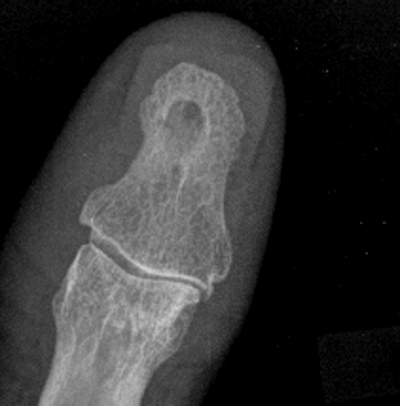

标题: X3013:男70岁,半年前拇指砸伤,近日拇指日夜疼痛。 [打印本页]

标题: X3013:男70岁,半年前拇指砸伤,近日拇指日夜疼痛。

男70岁,半年前拇指砸伤,近日拇指日夜疼痛。

植入性骨囊肿又称外伤性上皮植入性骨囊肿与创伤有关,病变多发生在末节指骨,病人都有数年以上的外伤史,手指软组织砸伤后,使小片上皮断离,并埋藏于皮下,而后逐渐移植于骨组织内,长时间增殖,生长,形成上皮样骨囊肿。

结合本例外伤史及征象,考虑上皮植入性囊肿可能性大。